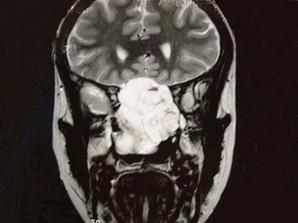

女性,41岁,鼻腔流脓涕3年,鼻部面部肿胀1年,近来加重,MRI检查如图,请选择最可能诊断 ( )